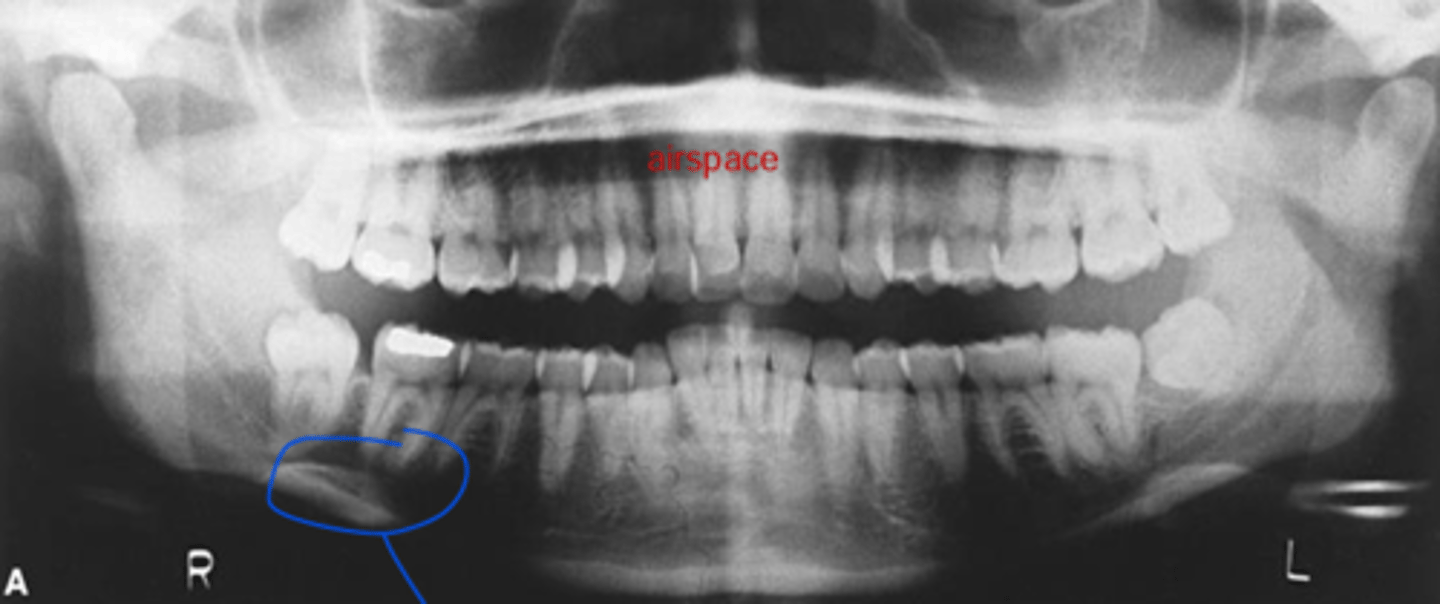

- patient didn't close all the way

- chin was down

- patient is too close to the film/receptor

What are the problems in this panoramic image?

A) mid-sagittal

What light needs to repositioned to fix this image?

B) Frankfort plane

C) focal trough